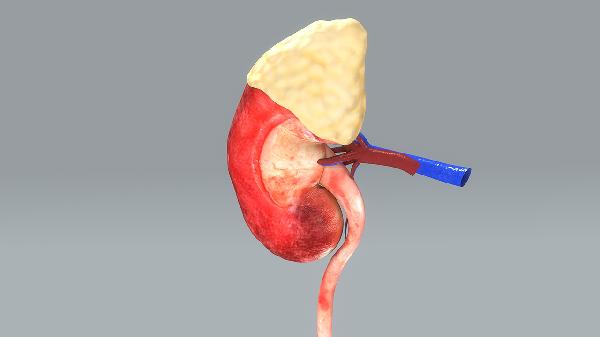

肝病是指發生在肝臟的病變。包括乙肝,甲肝,丙肝等多種肝病。是一種常見的危害性極大的疾病,應以積極預防為主。而對于已經罹患肝病的患者,則要樹立信心,選擇有效藥物積極治療。肝喜樂片經多年投入市場,獲得了患者廣泛的好評,使更多的患者能夠使用這一特效藥對抗病魔,提高了他們的生活和生存質量。肝喜樂片的療效明顯,總有效率達到92.7%,無明顯副作用,安全可靠。

清肝解毒片是一種中成藥,其含有五味子、靈芝、虎杖、葉下珠、火炭母、大黃、絞股藍、丹參、柴胡、六神曲、甘草。清肝解毒片是一種清熱解毒,利濕退黃的護肝藥物,但不具有抗病毒功能。清肝解毒片具有清熱解毒,利濕退黃的功效,適用于肝膽濕熱癥所引起的脅痛,黃疸,腹脹,納呆,惡心嘔吐,尿黃,苔黃等。